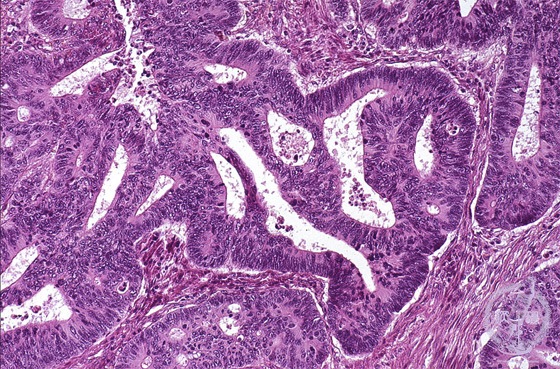

Microscopic view (H&E stain, medium power): Tubular adenocarcinoma is composed of small to medium sized tubules as well as cribriform growth (moderately differentiated).